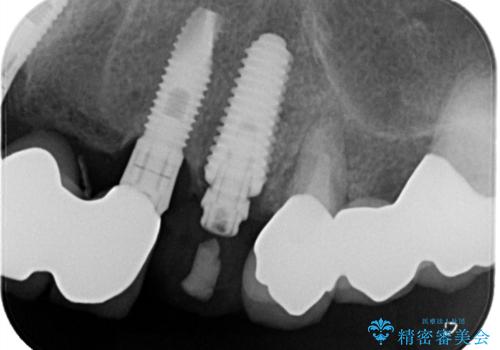

抜歯をしインプラント埋入と骨補填材を填入して仮歯までを1日で行う「抜歯即時埋入即時過重」の手術をし、3ヶ月後には、オールセラミックを被せて定期検診となりました。

遠方からの患者様で、短期間治療と治療中も仮歯が入っていたので審美的にも良かったと喜んでいらっしゃいました。